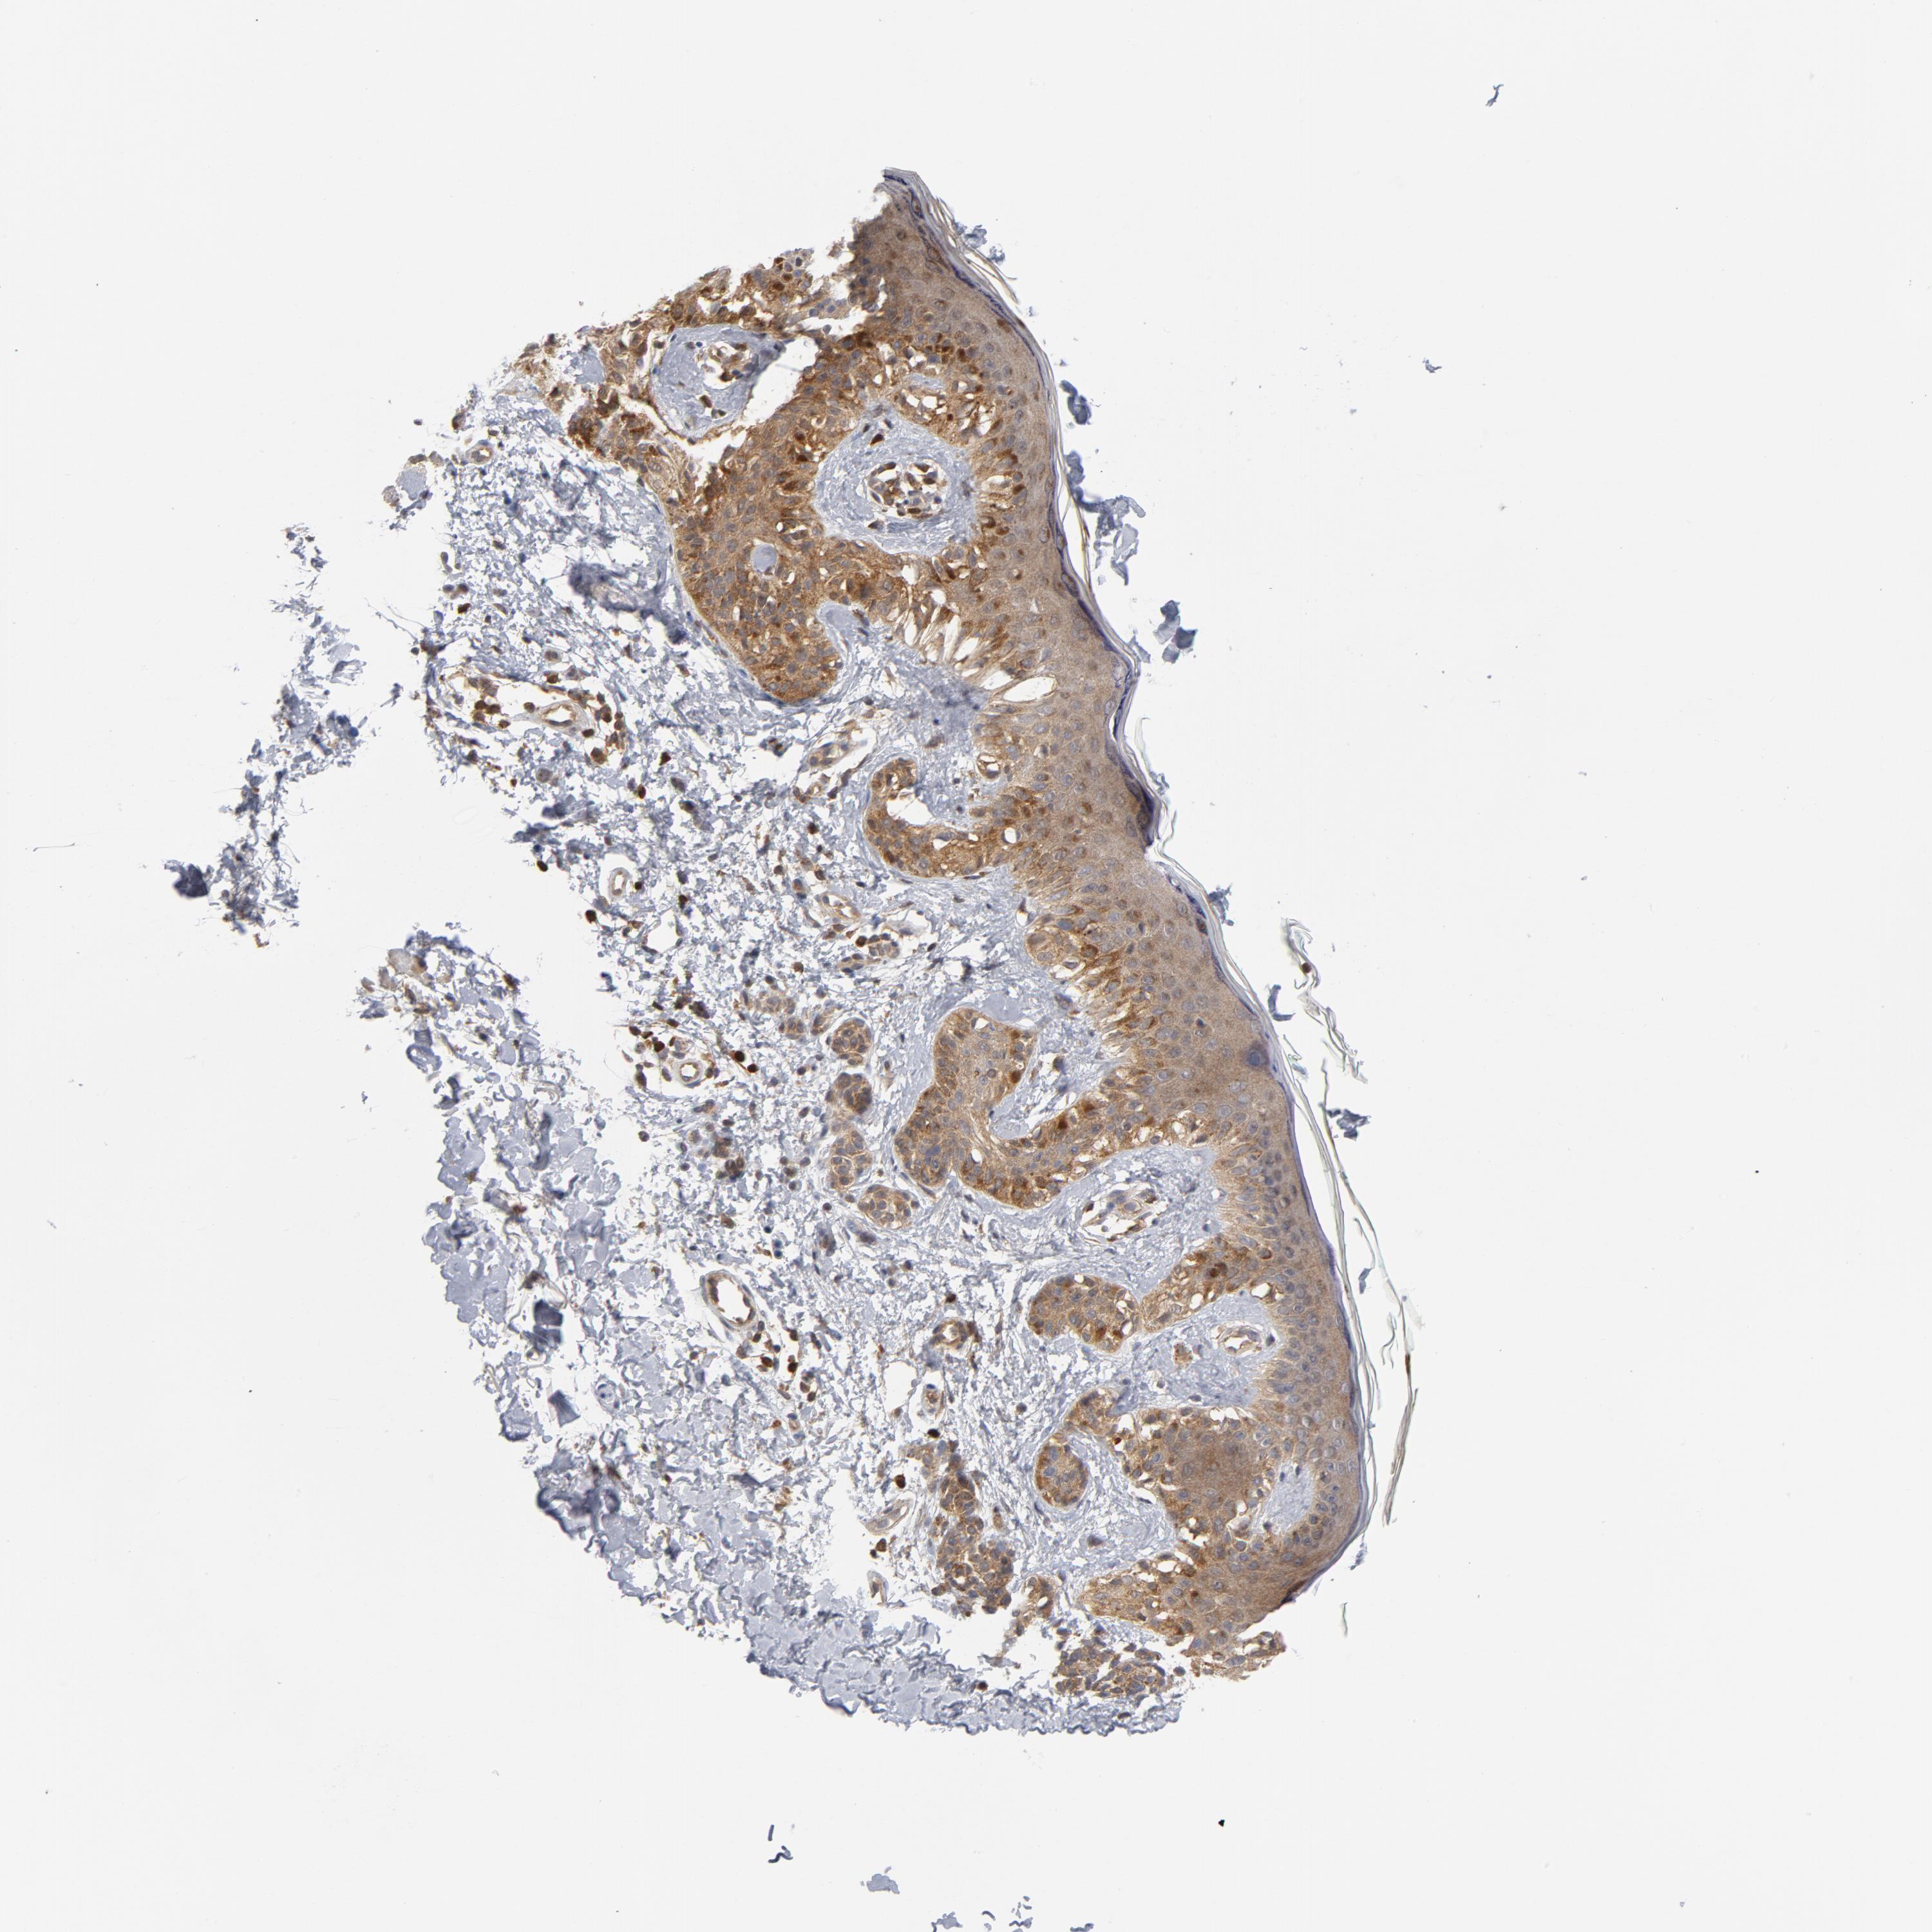

MELANOMA - Protein expressioni

A mouse-over function shows sample information and annotation data. Click on an image to view it in a full screen mode. Samples can be filtered based on level of antibody staining by selecting one or several of the following categories: high, medium, low and not detected. The assay and annotation is described here.

Note that samples used for immunohistochemistry by the Human Protein Atlas do not correspond to samples in the TCGA dataset.

Antibody stainingi

Antibody staining in the annotated cell types in the current human tissue is reported as not detected, low, medium, or high, based on conventional immunohistochemistry profiling in selected tissues. This score is based on the combination of the staining intensity and fraction of stained cells.

Each image is clickable and will lead to virtual microscopy that enables deeper exploration of all samples and also displays staining intensity scores, fraction scores and subcellular localization as well as patient and tissue information for each sample.

Antibody HPA071341

Antibody CAB004602

Staining

High

Medium

Low

Not detected

Intensity

Strong

Moderate

Weak

Negative

Quantity

>75%

75%-25%

<25%

None

Location

Nuclear

Cytoplasmic/membranous

Cytoplasmic/membranous,nuclear

Malignant melanoma, NOS

Malignant melanoma, Metastatic site